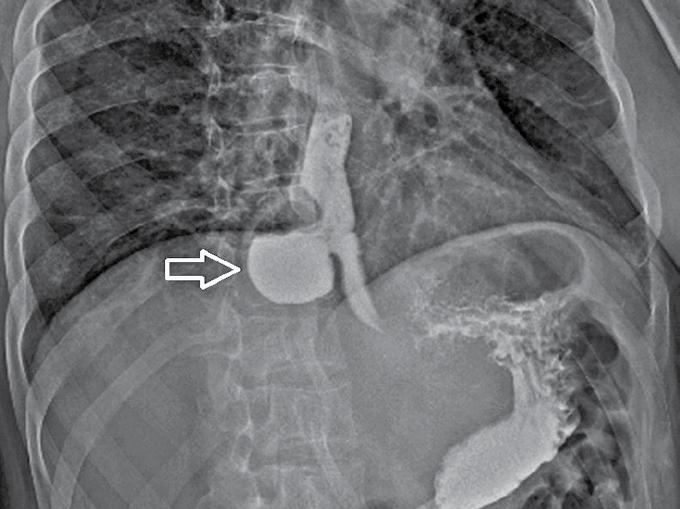

Diagnosticul se pune pe baza investigațiilor standard: endoscopie digestivă superioară și tranzit baritat (Fig 1). Manometria esofagiană ajută la caracterizarea motilității esofagiene, și la stabilirea diagnosticului etio-patologic. Uneori tomografia computerizată poate fi utilă pentru a descrie mai clar dimensiunile și

Fig 1. Tranzit baritat – diverticul esofagian epifrenic (săgeata galbenă) (Colecția clinicii de chirurgie generală și esofagiană – Sp Cl ”Sf Maria”)